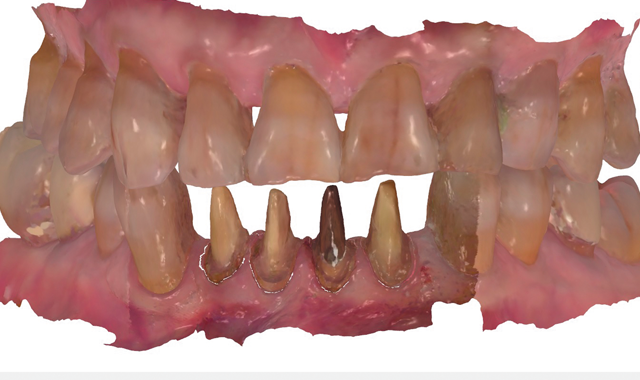

The patient returned a week later and expressed his satisfaction with the esthetic design of the four provisional units. During this appointment, the provisionals were now scanned with the intraoral scanner, and this “Pre-prep scan” was used to design the final restorations (Fig. 7). Once appropriately anesthetized, the provisionals were

then removed and the preparations cleaned with chlorohexidine 2%, after which they were also scanned (Fig. 8). Prior to a digital workflow, these impression processes would have required the use of trays and elastomeric impression materials, pouring of models and considerable chair time. In this case, the digital scans were used to create digital

preparation impressions and models.